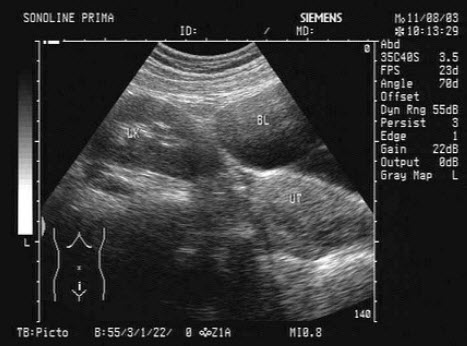

根据超声声像图,提示为()

A .肾下垂

B .肾发育不良

C .异位肾

D .马蹄肾

E .游走肾

根据超声声像图,提示为()

[单选题]根据超声声像图,提示为()A . 肾下垂B . 肾发育不良C . 异位肾D . 马蹄肾E . 游走肾

根据超声声像图,提示为()。

[单选题]根据超声声像图,提示为()。A . 肾下垂B . 肾发育不良C . 异位肾D . 马蹄肾E . 游走肾

根据超声声像图提示为

[单选题]根据超声声像图提示为A . 肾下垂B . 肾发育不良C . 异位肾D . 马蹄肾E . 游走肾